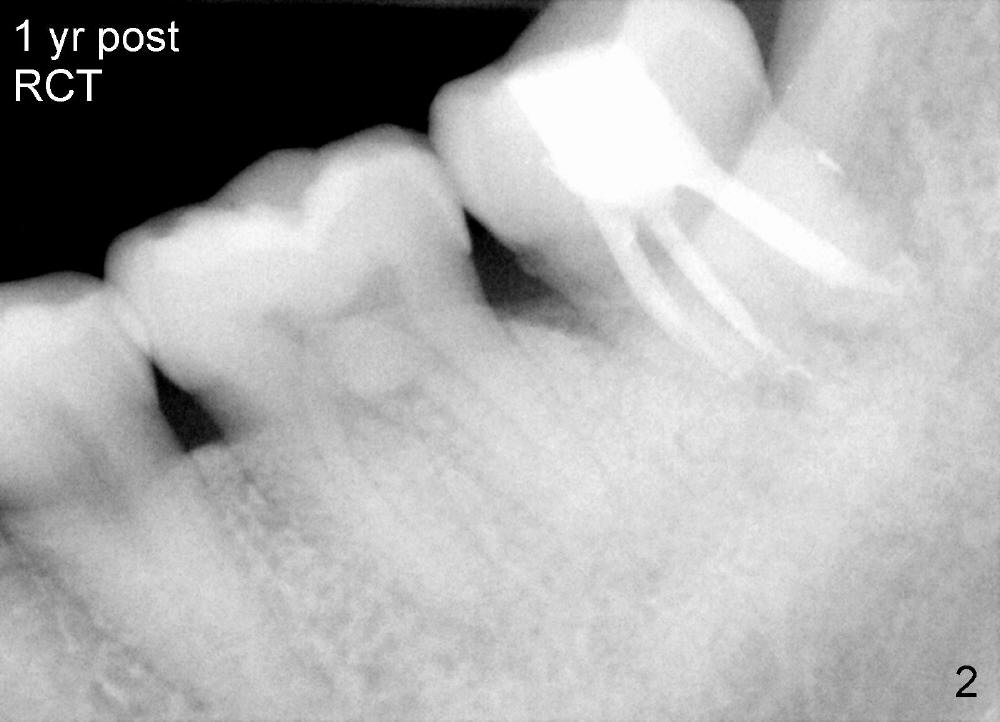

The lower left 2nd molar of a 45-year-old lady has perio-endo disease (Fig.1). The patient is not only very nervous, but also active in gag reflex. It is difficult to take good preop PA (Fig.1 *: ). Root canal therapy is performed. A relatively good PA is taken 1 year postop, again due to gap reflex (Fig.2). The tooth is still nonsalvageable (Fig.3). The last PA is taken 3.5 years before extraction and immediate implant. Infiltration anesthesia is administrated first. The patient experiences pain during early stage of osteotomy, but she does not report readily. Block anesthesia is added. Intraop PAs are taken with difficulty (Fig.4,5 with #1 sensor; 5 mm tap in place). Invasion of the inferior alveolar canal is not noted (Fig.5 dashed line). Oozing is a little more than expected. This is ignored. A 7x14 mm tapered implant is placed; the upper border of the inferior alveolar canal is not intact (Fig.6). Paresthesia area is defined next day (Fig.7). The implant is reversed for a few turns. Paresthesia area is reduced 19 days later (Fig.8). The implant is not stable. Follow up PAs are taken with difficulty (Fig.9-11). It appears that a shorter cylindrical implant is more appropriate for this case (Fig.11). The implant is stabilized with splinting with questionable result (Fig.12).